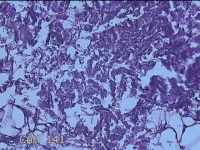

外阴部包块

性别

女

年龄

37岁

临床诊断

皮脂腺囊肿

一般病史

外阴部起包块一月余。

标本名称

大体所见

灰白暗红色包块2.3x1.8x0.8cm一个,表面糜烂,切开包块呈实性,切面灰白淡黄色,质软。

有那么点像脂肪瘤。